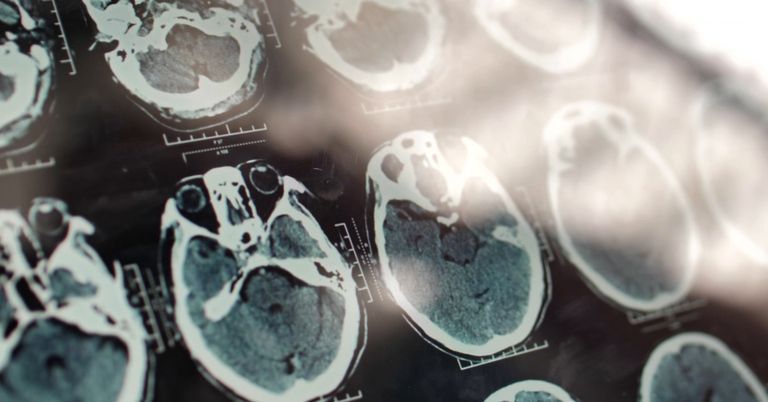

Hoffnung gegen Alzheimer: Der Wirkstoff Donanemab, der nun vom US-Pharmakonzern Ely Lilly vorgestellt wurde, zeigt eine bislang noch nie dagewesen starke Wirkung gegen den geistigen Abbau.